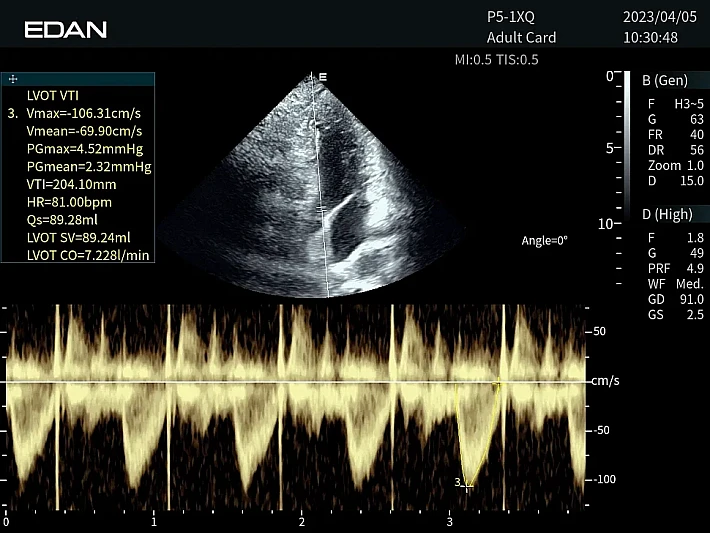

Медицинское оборудование и сервисное обслуживание